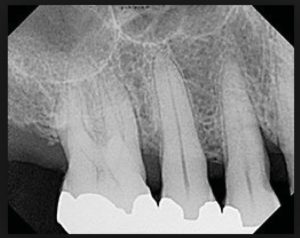

As previously mentioned, a dull or compromised scaler can lead to increased discomfort and decreased tactile sensitivity due to increased lateral pressure and number of strokes needed to remove the deposits. The cost of burnishing calculus, resulting in iatrogenic and supervised progression of periodontal disease when patients are placing their oral health in our hands cannot be measured (Fig 3,4). Breakage of a blade in a patient’s mouth, with possible need for surgical intervention due to using an over-worn working end is a preventable situation with a simple and quick check of the working end against a template.